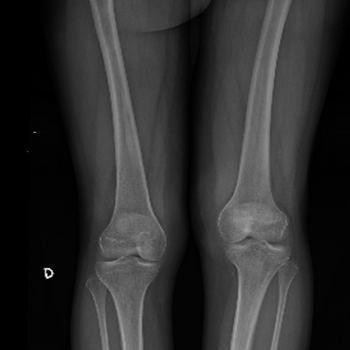

con clavo Precice

con clavo Precice

El equipo, formado por los Dres. Javier Alonso, Juan Cabello y Carlos Miranda, ha llevado a cabo con éxito más de 30 procedimientos quirúrgicos de Alargamiento con clavo intramedular en Madrid, siendo el equipo que más experiencia tiene en España y uno de los grupos con más experiencia en Europa.